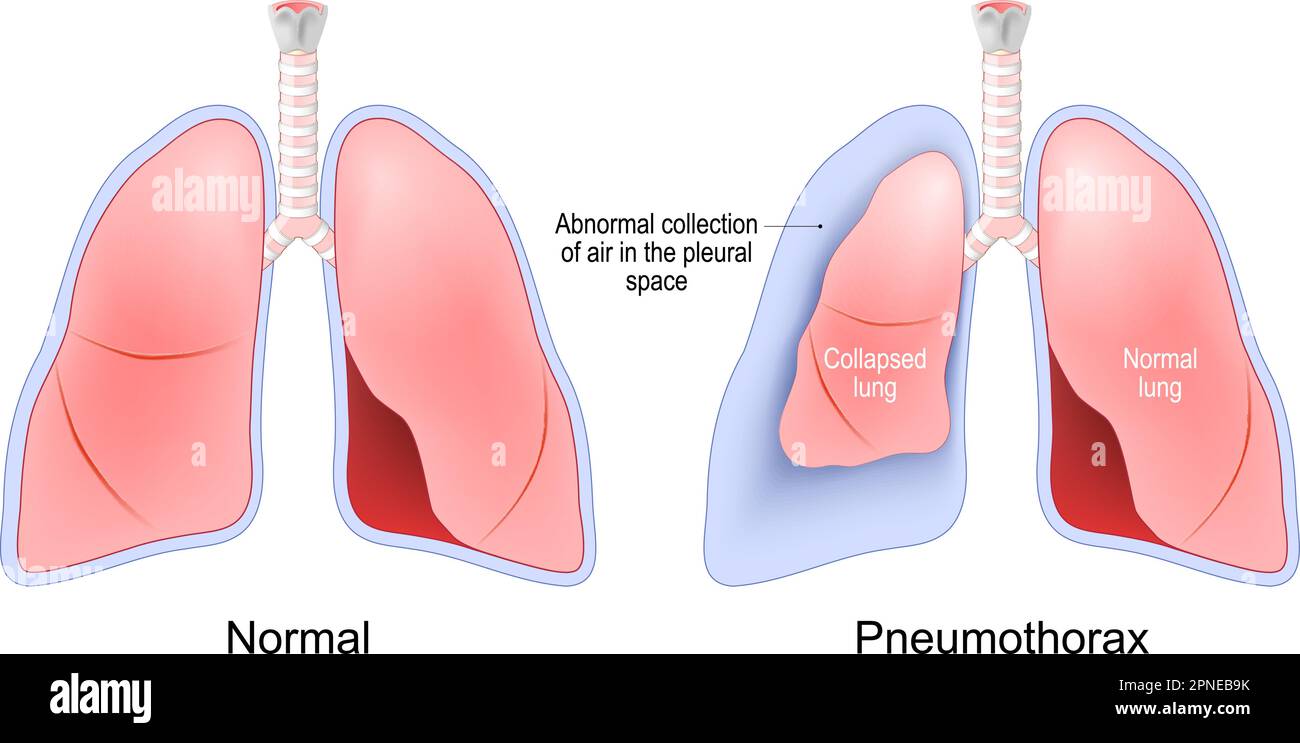

RF2PNEB9K–Pneumothorax. accumulation d'air entre le poumon et la cavité thoracique. Normal, et les poumons se sont effondrés. Système respiratoire humain. Illustration vectorielle